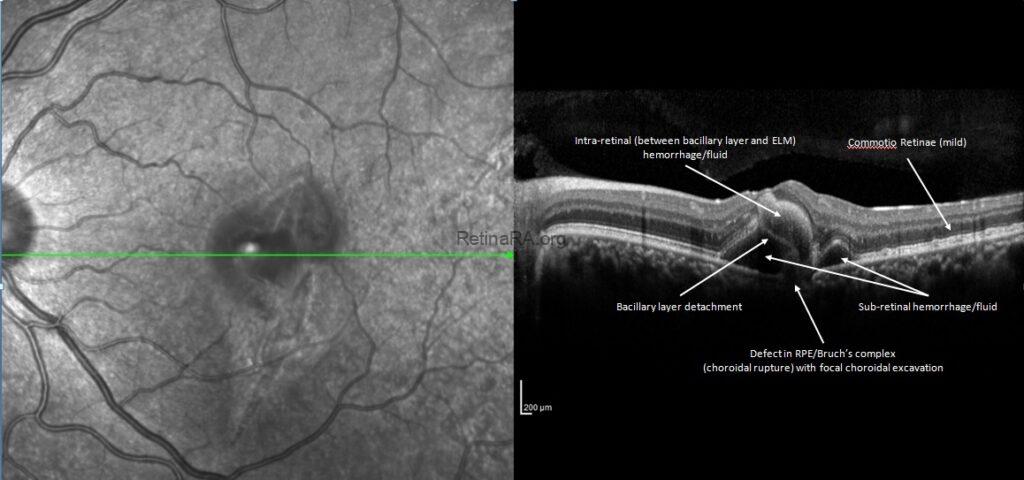

Dilated fundus examination of the left eye showed commotio retina, widespread intraretinal hemorrhage and fluid with macular involvement and choroidal rupture.

The spectral domain optical coherence tomography (OCT) imaging revealed defective retina pigment epithelium-Bruch’s membrane complex with a focal choroidal excavation, mild commotio retina, cystic subretinal hemorrhage areas, bacillary layer detachment and intraretinal hemorrhages that located between bacillary layer and external limiting membrane.